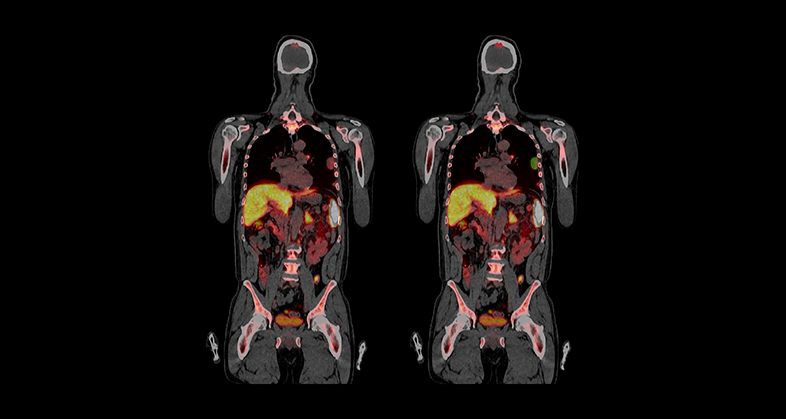

We provide automated segmentation methods for lesions and organs in whole body PET/CT examinations. The most frequent clinical scenarios are lymphoma and multiple myeloma, extracting lesion-level features, which, combined at the patient level, can help in predicting treatment response in standard or advanced therapies as well as other phenomena like cytokine release syndrome (CRS) or Immune effector cell-associated neurotoxicity syndrome (ICANS) in cell therapies such as Chimeric Antigen Receptor T-cell therapies (CAR-T).